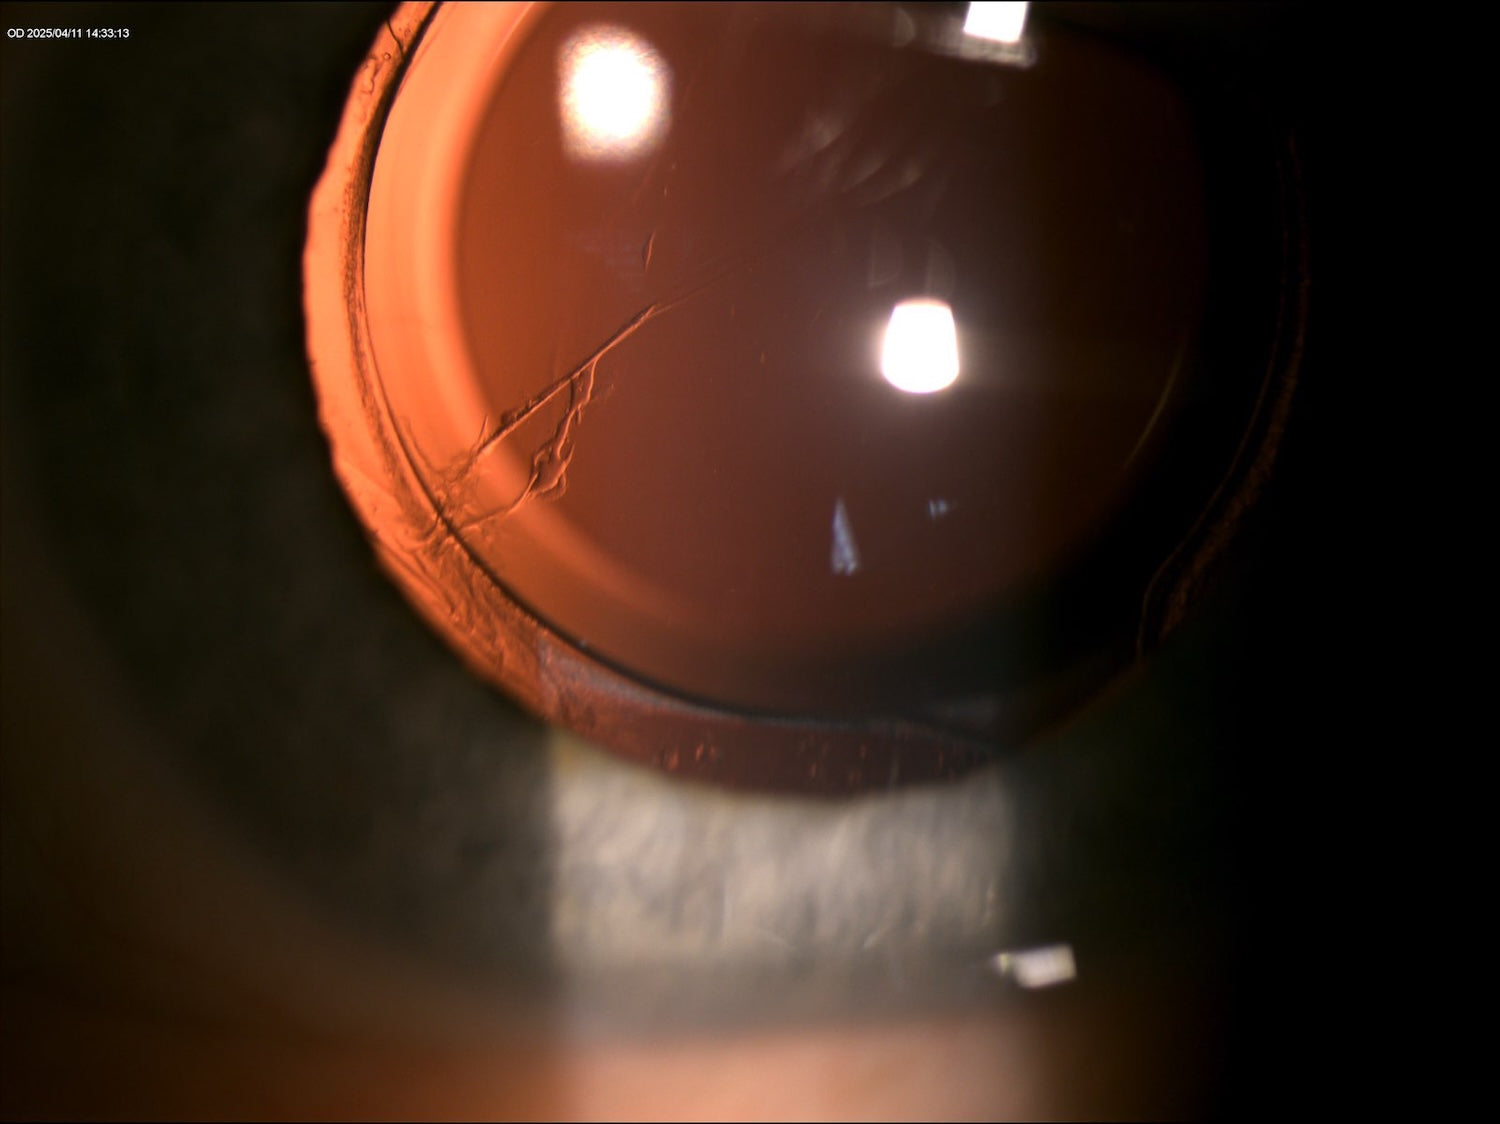

Technika retroiluminácie pre vizualizáciu defektov či opacít na šošovke / IOL.